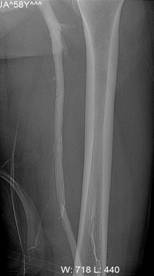

4、下肢动脉闭塞症

各种原因致动脉血管阻塞,包括下肢动脉硬化闭塞症、糖尿病足、下肢动脉栓塞等。动脉阻塞后远侧肢体缺血,出现疼痛、肤温减低、肤色苍白、无脉等症状,严重者趾端坏死,甚至需要截肢。动脉闭塞的治疗主要是施行介入手术,于阻塞的动脉血管内以导管、导丝开通阻塞段,然后行溶栓、球囊扩张、支架成型等治疗。对于膝关节以上的动脉血管闭塞,介入再通成功率达90%以上,而对于膝下动脉血管成功率仅为60%~70%。动脉闭塞好发于老年人,多合并冠心病、高血压、脑梗塞、糖尿病等慢性病变,手术风险相对较高,我科自2013年始,对高龄、多合并症的下肢动脉闭塞患者,采取先行静脉药物治疗观察疗效,疗效不满意者再行介入手术的整体治疗方案。药物治疗以疼痛消失、行走距离明显改善为目标,现有病例统计,总有效率达90%以上,使多数高危患者避免了手术的风险;对于药物治疗不满意的患者再行考虑是否行介入手术治疗,而介入手术治疗中尽可能避免支架置入治疗,规避支架后再闭塞、断裂等风险。

病例介绍:

窦××,男,79岁,“右足部疼痛伴局部破溃半年”入院,间歇性跛行200米,右踝关节局部1.5×1.5cm2溃疡,第5趾底1.0×1.0 cm2溃疡,表面渗出物。糖尿病病史23年,高血压病史23年,脑梗塞病史7年。下肢动脉CTA示双下肢动脉广泛斑块形成,多发狭窄,双侧膝下动脉间断显示,大部闭塞。经药物治疗10天,疼痛消失,可自行持续行走1000米以上双下肢无不适,原足趾部溃疡愈合,踝关节部溃疡结痂。